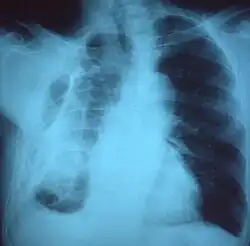

A fibrothorax can typically be diagnosed by taking an appropriate medical history in combination with the use of appropriate imaging techniques such as a plain chest X-ray or CT scan.[3] These imaging techniques can detect fibrothorax and pleural thickening that surround the lungs.[7] The presence of a thickened peel with or without calcification are common features of fibrothorax when imaged.[3] CT scans can more readily differentiate whether pleural thickening is due to extra fat deposition or true pleural thickening than X-rays.[3]

If a fibrothorax is severe, the thickening may restrict the lung on the affected side causing a loss of lung volume.[7] Additionally, the mediastinum may be physically shifted toward the affected side.[3] A reduction in the size of one side of the chest (hemithorax) on an X-ray or CT scan of the chest suggests chronic scarring.[6] Signs of the underlying disease causing the fibrothorax are also occasionally seen on the X-ray.[6] A CT scan may show features similar to those seen on a plain X-ray.[7] Lung function testing typically demonstrates findings consistent with restrictive lung disease.[6]

Extensive left-sided fibrothorax -

Chest radiograph displaying inhomogeneous opacification of the left half of the chest that is fibrothorax -